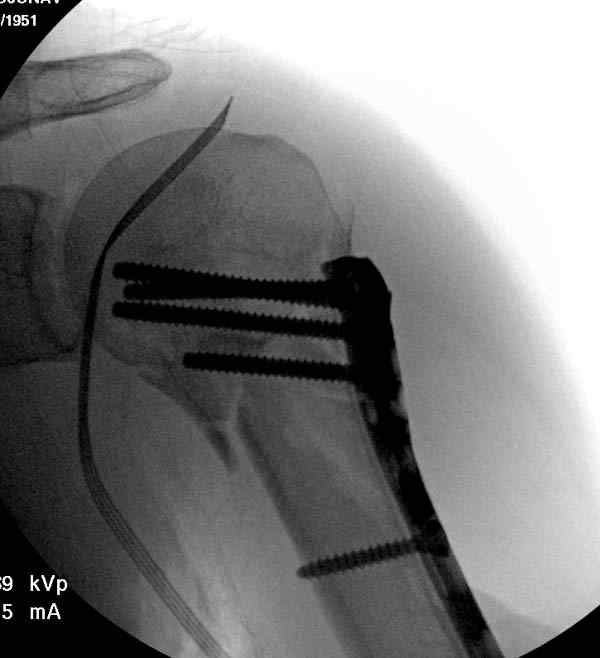

Здесь пример открытой репозиции 57 летнего с переломом плеча (1,2) смещение обнаружено на интероперационном снимке. При нормальной прямой проекция (3) угловое смещение обнаружили в аксиальной проекции (4)

После устранения смещения пластина установлена выше (5,6,7) и финальные снимки (8,9,10)

Подбор импланта тоже имеет значение, например многие импланты направлены для фиксации перелома без учета ротаторной манжетки. Предпочтительными являются низко сидящие полиаксиальные пластины, где верхние шурупы можно проводить под углом в 120 градусов. (11)